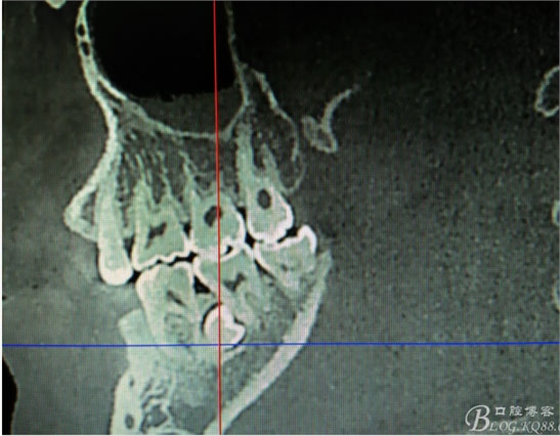

患者、盧xx、男、19歲。主訴:左側(cè)下頜乳磨牙未脫落,要求檢查。??茩z查:左側(cè)下頜第二乳磨牙有充填物。無松動(dòng),全景片檢查。35移位至36、37之間。頰舌側(cè)均不能觸及隆起。CBCT檢查:35位于36、37的舌側(cè)。表面骨質(zhì)約2mm左右。35完全骨埋伏,36的遠(yuǎn)中牙根疑是吸收。建議35暫觀察。置留不取。患者要求拔除擔(dān)心壓迫36牙根或者發(fā)生囊性變。術(shù)前簽手術(shù)同意書。